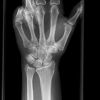

Handgelenk a.p.

1. Möglichkeit:

Frage nach Bandruptur: gewinkelter Vorderarm liegt flach auf dem Tisch, Handgelenk liegt mit der volarer Seite auf der Kassette, D3 verläuft gestreckt in Richtung Radius.

2. Möglichkeit:

Frage Fraktur: Finger locker gebeugt, Hand nach lat. abduziert (abgespreizt).

Senkrecht auf Objektmitte und Filmmitte.

Darstellung der Handwurzel- und Unterarmknochen, bei Fragestellung von Epiphysenlösung, Grünholz- oder Os scaphoideumfraktur. Zur Beurteilung der Knochenkerne bei Kindern werden Vergleichsaufnahmen notwendig, bei Verdacht auf Subluxation des Os Lunatums, Zusatzaufnahme in Flextion und Reflextion der Hand notwendig (siehe Stressaufnahme).

Qualitätskriterien

Vollständige Abbildung der Metacarpalia, Handwurzelknochen und distaler Unterarm.